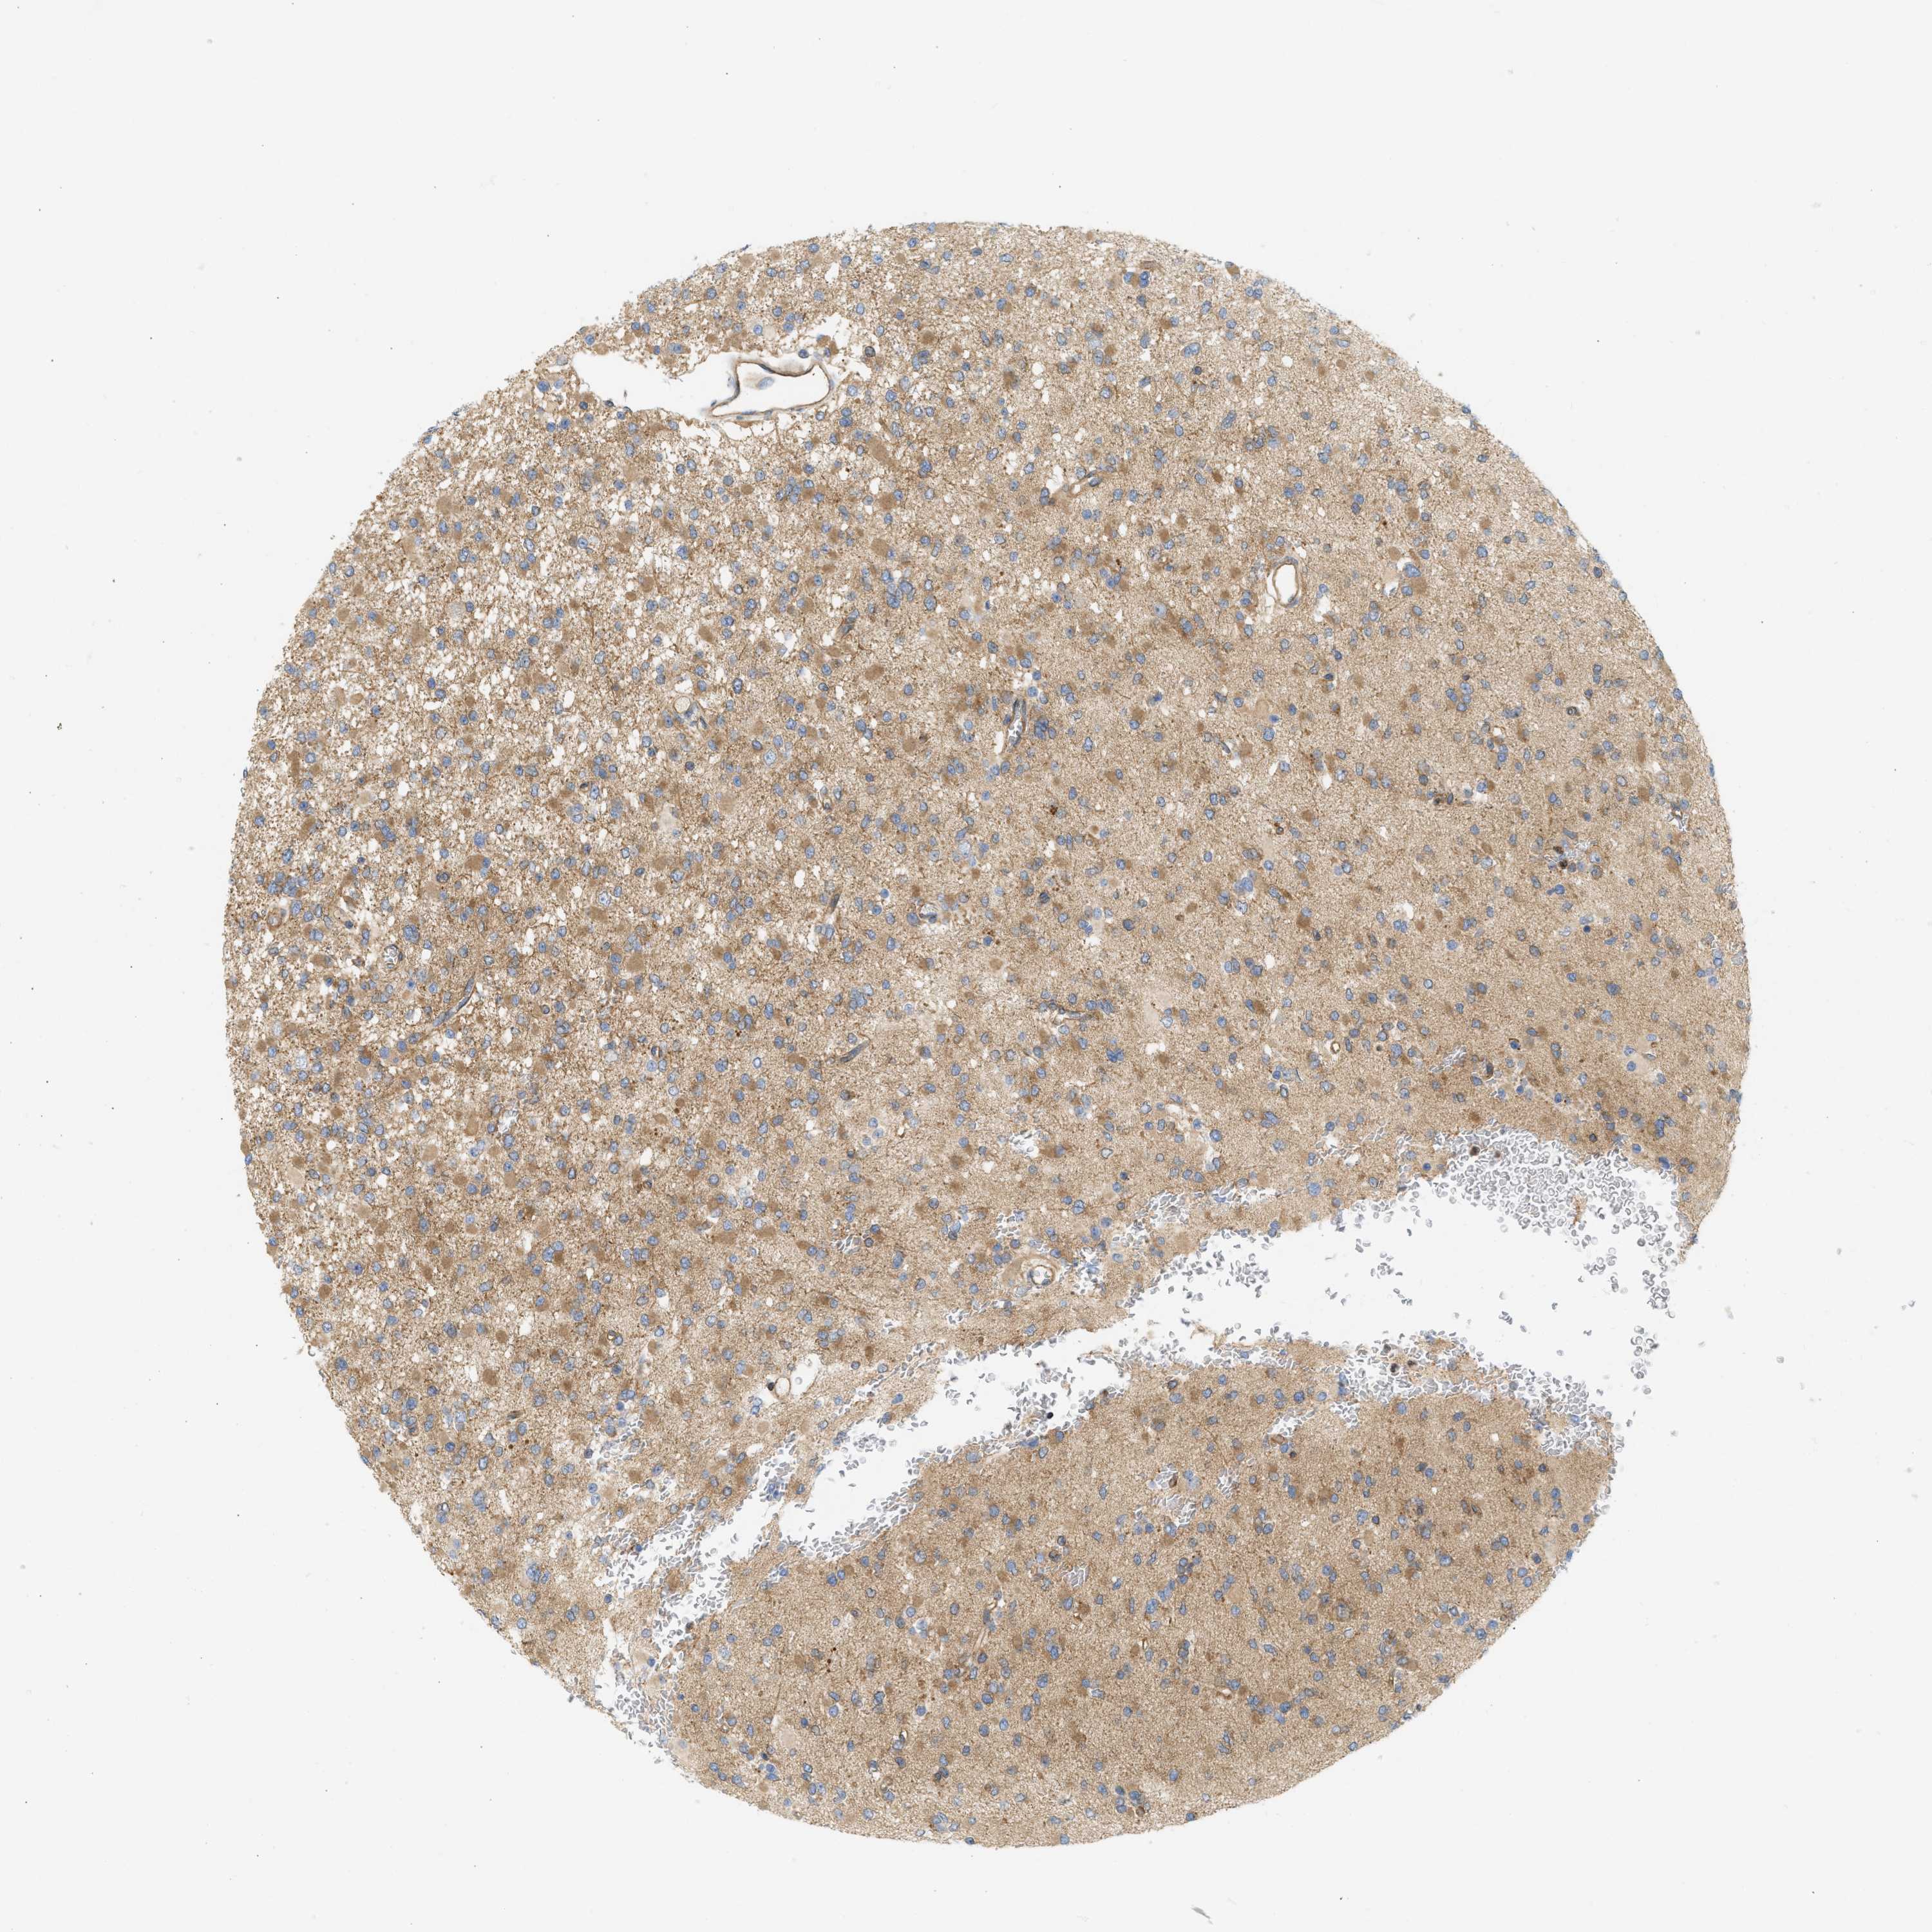

GLIOMA - Protein expressioni

A mouse-over function shows sample information and annotation data. Click on an image to view it in a full screen mode. Samples can be filtered based on level of antibody staining by selecting one or several of the following categories: high, medium, low and not detected. The assay and annotation is described here.

Note that samples used for immunohistochemistry by the Human Protein Atlas do not correspond to samples in the TCGA dataset.

Antibody stainingi

Antibody staining in the annotated cell types in the current human tissue is reported as not detected, low, medium, or high, based on conventional immunohistochemistry profiling in selected tissues. This score is based on the combination of the staining intensity and fraction of stained cells.

Each image is clickable and will lead to virtual microscopy that enables deeper exploration of all samples and also displays staining intensity scores, fraction scores and subcellular localization as well as patient and tissue information for each sample.

Antibody HPA017286

Staining

High

Medium

Low

Not detected

Intensity

Strong

Moderate

Weak

Negative

Quantity

>75%

75%-25%

<25%

None

Location

Nuclear

Cytoplasmic/membranous

Cytoplasmic/membranous,nuclear

Glioma, malignant, Low grade

Glioma, malignant, High grade